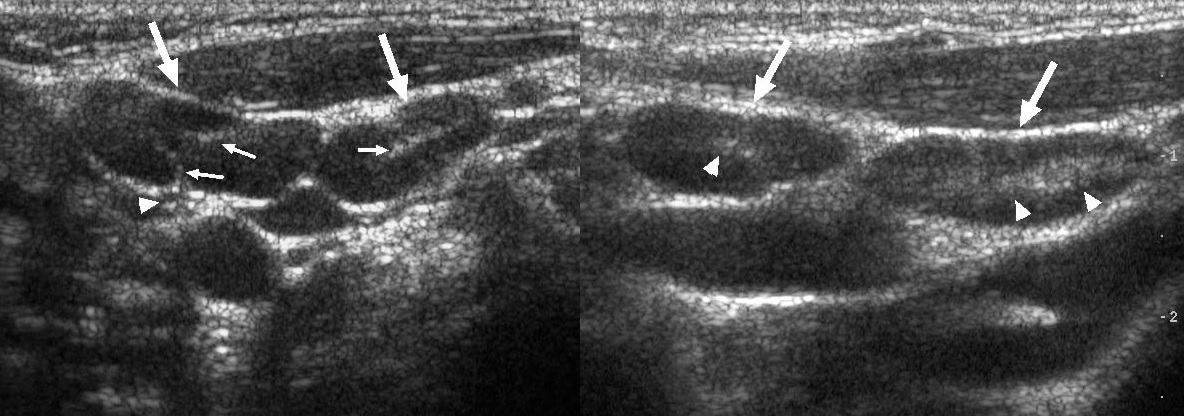

УЗИ лимфоузлов при лимфоме Ходжкина

Раздел: Образы вокруг